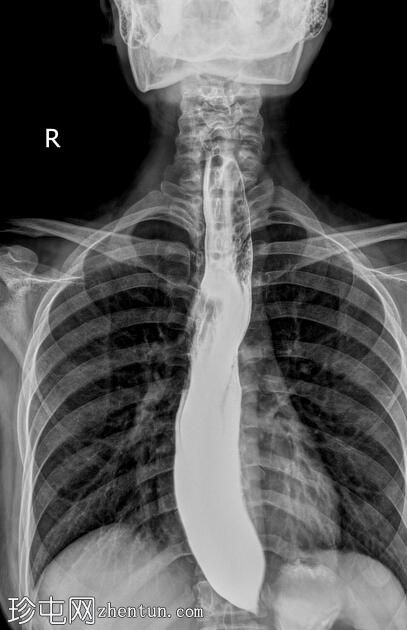

透视检查

斜位

正位

食管扩张,远端平滑狭窄并呈锥形(鸟嘴状),符合贲门失弛症的特征性表现

食管黏膜形态正常,无异常或溃疡

未见食管裂孔疝

钡餐检查显示食管扩张,远端狭窄并呈锥形,形成符合贲门失弛症特征的鸟嘴状外观。